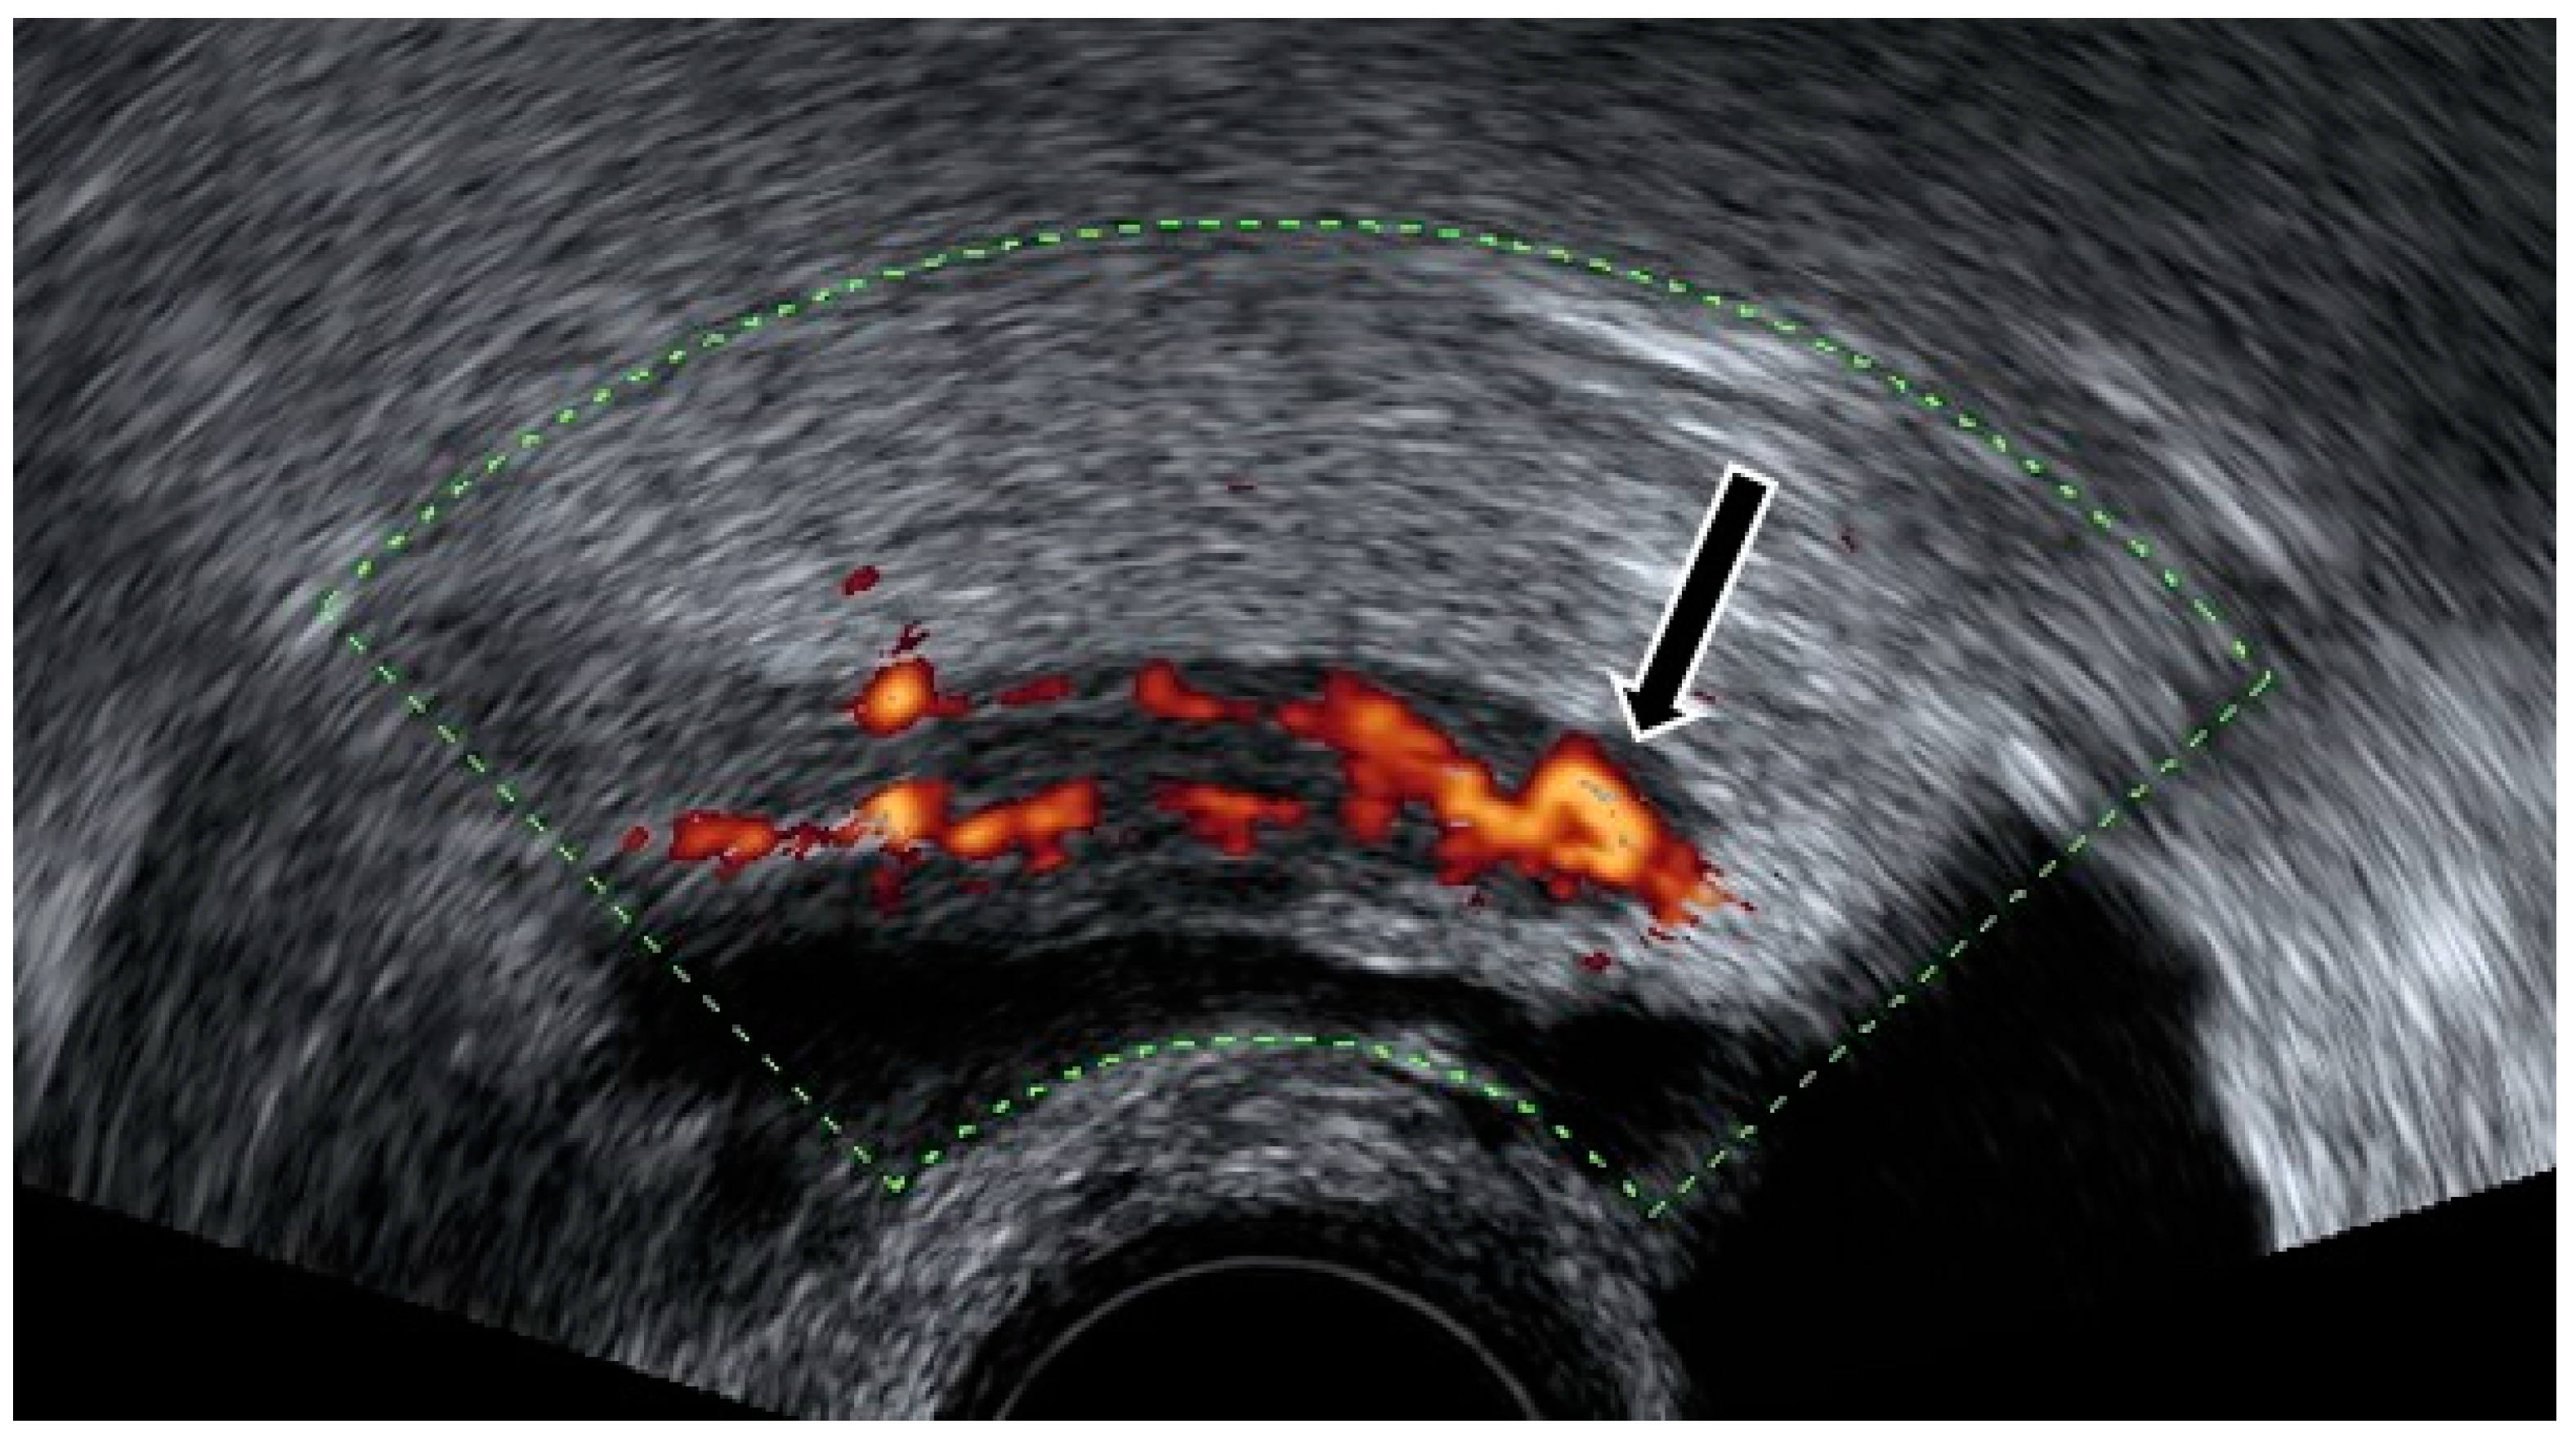

4.1. Pelvic Congestion